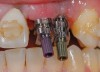

Figure 7  (Case 1) Immediate placement of No. 11. Note stent design to allow for lingual set screw access.

Figure 7

Figure 8  (Case 1) Additional augmentation with demineralized freeze-dried bone allograft at the time of implant placement.

Figure 8